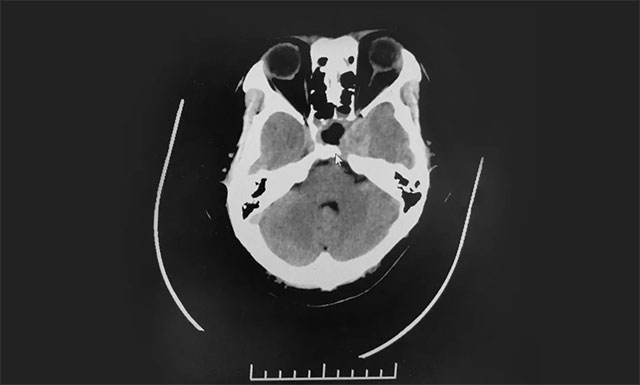

▲ 术后影像显示肿瘤被切除

在制定详细手术方案并充分完善术前准备后,7月24日,李士其教授在吴治群博士、黄秀夫医生协助下经蝶窦入路成功为患者进行了手术。术中,在蔡司显微镜(双荧光)下,见淡红色肿物,质软,其外有包膜覆盖。李士其教授在充分保护好海绵窦、颈内动脉、视神经等结构前提下,将鞍内可见肿瘤全部切除,并留取肿瘤送检病理。手术顺利完成,术中只失血约10毫升。

目前,患者视力明显改观。后期还将辅以药物及放射治疗。